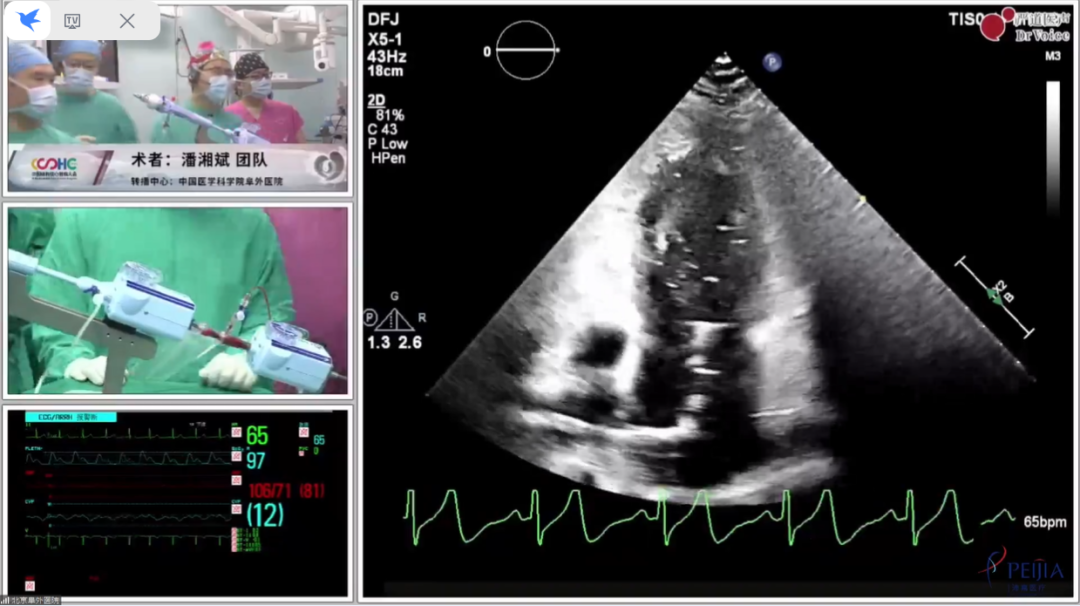

在房间隔穿刺时,手术团队使用自主研发的超声引导专用介入导丝,该导丝头端呈纺锤形,在TTE下清晰可见,精准定位房间隔穿刺部位,波兰Zenon Hucze等专家给予了高度评价。

将CDS送入肺静脉